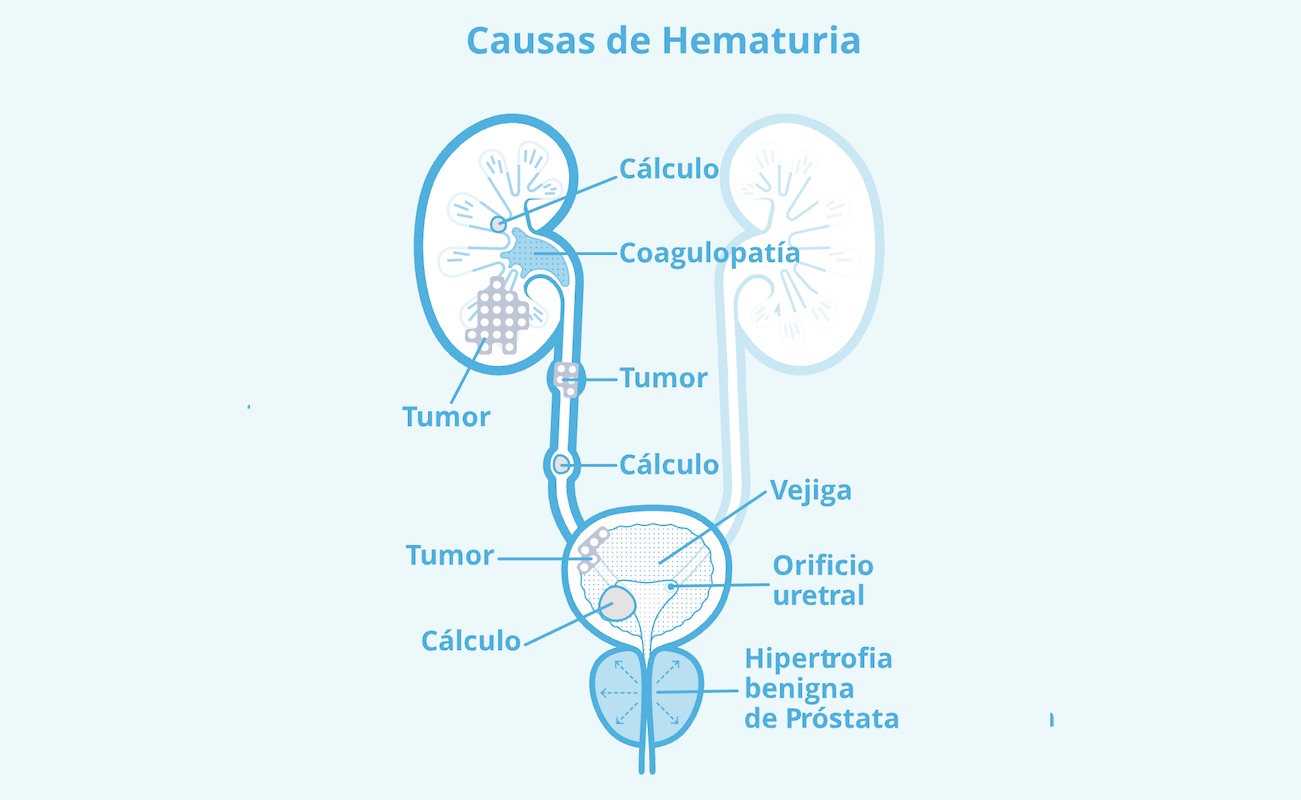

La uretromeatotomía es un procedimiento quirúrgico ambulatorio que se realiza para ampliar el meato uretral y el segmento distal de la uretra cuando existe una estrechez que dificulta la salida normal de la orina 🚻

Es una intervención frecuente en casos de estenosis del meato o estenosis uretral distal.

🔎 ¿Cuándo está indicada?

El urólogo puede recomendarla si presentas:

✔️ Chorro urinario fino o débil

✔️ Dificultad para iniciar la micción

✔️ Dolor o ardor al orinar

✔️ Desviación del chorro

✔️ Infecciones urinarias repetidas

Estos síntomas no deben normalizarse, ya que pueden progresar.

⚠️ La evaluación especializada es clave para confirmar el diagnóstico y descartar otras causas de obstrucción urinaria.